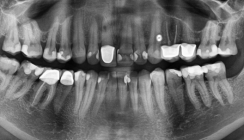

Zunächst wurden aus den Autoren-Praxisjahren 1995, 1996, 1997 die verwendeten WF-Mittel N2 (n = 50) und Diaket (n = 28) hinsichtlich der Survivalrate miteinander verglichen. Alle endodontischen Behandlungen – ob mit N2 oder Diaket – wurden in exakt derselben Art und Weise durchgeführt. Dieses Vorgehen beinhaltete: relative Trockenlegung mit Watterollen, starke manuelle Kanalaufbereitung nur mit Reamern in der „Crown-down“-Technik, keine Kanalspülungen, Lentulo-Applikation des WF-Mittels, WF-Verdichtung mittels Guttaperchastift (single cone), nach der „WF-Aufklappungsschnitt und Bohrer (Komet H1 014)“-Fistulation unter Belassung von Granulationsgewebe und Überfüllung, ein bis zwei Nähte, kein Drain.

Bei Aufnahme der WKB zeigten 54 % der N2-Zähne und 57 % der Diaket-Zähne eine apikale Parodontitis (AP). Eine spätere Röntgenkontrollaufnahme lag nach N2 in 39 Fällen (78 %), nach Diaket in 20 Fällen (71,4 %) vor. Diese Aufnahmen wurden wie folgt diagnostiziert: Erfolg nach N2 in 35 Fällen (89,7%), nach Diaket in 14 Fällen (70 %), alle Revisionen mit Erfolg, Misserfolg nach N2 in 2 Fällen (5,1 %), nach Diaket ebenfalls in zwei Fällen (10 %), fraglich/unsicher nach N2 in zwei Fällen (5,1 %), nach Diaket in vier Fällen (20 %).

Bei Aufnahme der WKB wurde bei den TR-Fällen 19-mal (57,6 %), bei den WR-Fällen 20-mal (60,6 %) ein AP diagnostiziert. 25 der 33 Paare (75,8 %) erfuhren eine röntgenologische Nachkontrolle. Die TR-Fälle zeigten in 22 Fällen (88 %) keinen pathologischen Apikalbefund, in drei Fällen ein fragliches Ergebnis. Die WR-Fälle wurden 18-mal (72 %) als apikal ohne pathologischen Befund beurteilt. Drei Fälle wurden als fraglich und vier (12,1 %) als Misserfolg befundet – die letzteren alle mit einer initialen AP. Die acht TR-Revisionsfälle wurden als Erfolg bewertet, zwei der sechs WR-Revisionsfälle als Misserfolg. Nach TR traten keine röntgenologischen, jedoch drei klinische Misserfolge ein: nach 1 und 103 Tagen mit